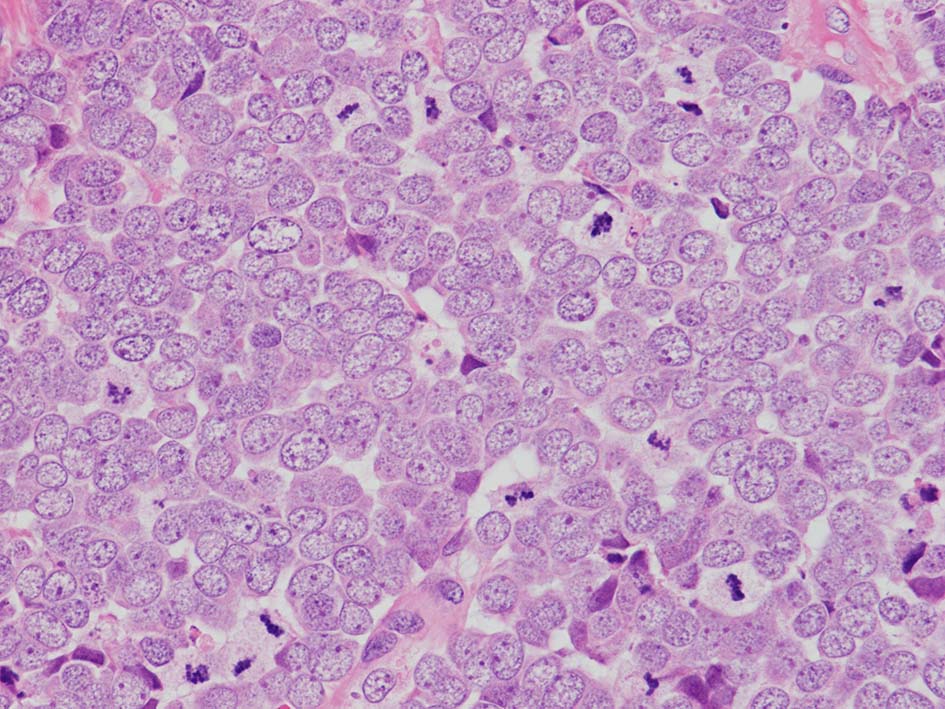

典型的な腫瘍細胞は円形, 卵円形の比較的均一な形態で「salt-and-pepper」と称される微細顆粒状クロマチンを有する小型円形核をもつ. MCPyV陽性例が均一な小型円形核を呈する傾向があり, 陰性例では, 核多形性が目立つととする報告がある.

trabecular type, intermediate type, samll cell typeの3パターンの組織型に分類されているがしばしば混在している.

- trabecular typeは円形から多稜形の腫瘍細胞が索状に配列, 3形のなかで腫瘍細胞がもっとも大きく, 円形核と比較的豊富な細胞質をもつ.

- small cell typeは濃いクロマチン, 多形性を示す核をもつN/C比大の小型腫瘍細胞がびまん性に増殖する.

- intermediate typeではtrabecular, samll cell typeの中間の腫瘍細胞サイズを示す. 組織型としてはもっとも多い.

血管を間質にしてround cellsが索状に増殖する所見. rossett様配列がある. CK20は特徴的な dot-like patternを示す. クリックで大きな画像が見られます.